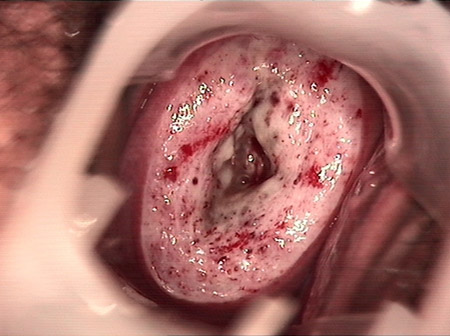

婦科leep錐切手術(shù) CIN2-3

• CIN 2-3 leep術(shù)后CIN 2-3 leep術(shù)后